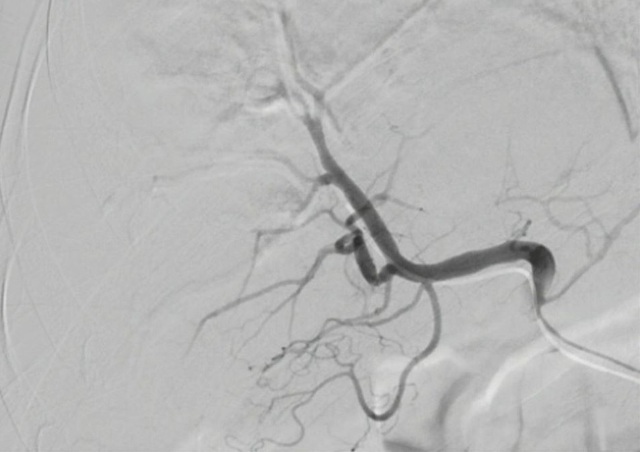

Sau hội chẩn nhanh, các bác sĩ quyết định thực hiện kỹ thuật tắc mạch để cầm máu cho người bệnh. Phương pháp trên không cần mổ hở, thay vì gây mê, bệnh nhân được gây tê tại chỗ. Dưới hướng dẫn của máy xóa số nền DSA, bác sĩ luồn một ống thông nhỏ từ mạch đùi đến vị trí chảy máu. Ê kíp can thiệp tiến hành bơm thuốc cản quang, chụp hình để xác định vị trí chảy máu trong gan. Sau đó các bác sĩ đã luồn một ống thông siêu nhỏ để tiếp cận các nhánh động mạch tổn thương và dùng vật liệu tắc mạch, cầm máu.

Bác sĩ Nguyễn Thanh Long, khoa Chẩn đoán hình ảnh - phẫu thuật viên chính cho biết: “Trước đây, hầu hết các ca tổn thương, dập, vỡ gan đều phải phẫu thuật khâu gan kèm chèn gạc cầm máu. Bệnh nhân phải trải qua một cuộc phẫu thuật và thời gian hậu phẫu lâu hơn, nguy cơ gặp phải các biến chứng về gây mê. Bằng kỹ thuật xâm lấn tối thiểu, chỉ trong vòng 30 phút, ca thủ thuật đã thành công tốt đẹp. Đây là phương pháp can thiệp kỹ thuật cao giúp cầm máu ngay lập tức và giúp vùng gan vỡ chóng lành. 3 ngày sau thủ thuật, sức khỏe của bệnh nhân đã bình phục rất tốt".